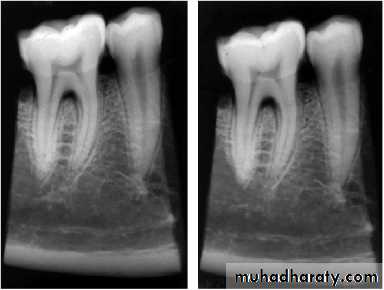

Radiographs IMPORTANCE

Provides information on the extent of caries in to the pulpNo. of root canals and accessories

The course & shape of the canals

Length of the root

CalcificationsResorptions

PDL status8. Nature of periapical area & alveolar bone

9. Root fractures10. Differentiation of pathosis

11. Location of perforations12. Post obturation evaluation

13. Evaluate healing after RCT

14. Medico legal recordsLimitations1-2 D image of 3D object

• State of pulpal health can not be ascertained

• P/A pathology is evident only after much destruction(33%)• Vertical root fracture can not be diagnosed

• Bony trabculae misinterpreted for horizontal root #

• Extend of caries is usually less than the actual extent as is true for P/A pathology

Anatomic structure can mimic P.A. pathology